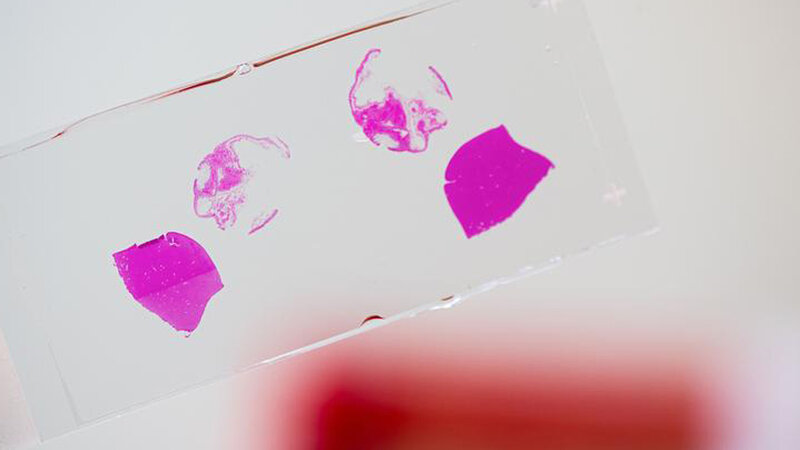

Ausgelöst wird die Nekroptose, wenn es zur Aktivierung eines Proteins namens RIPK3 kommt, das dann Prozesse in der Zelle in Gang setzt, die den Zelltod auslösen. Anhand von Zellkulturen stellten die Wissenschaftlerinnen und Wissenschaftler fest, dass die Leukämie einen besonders schweren Verlauf nimmt, sobald man RIPK3 in den LICs blockiert. Die Krebszellen überlebten dann besonders lange, teilten sich stark und bildeten sich zu funktionslosen Blutkörperchen (Blasten) um. „Daraus schließen wir, dass es besonders aggressiven Krebszellen gelingt, RIPK3 zu blockieren“, sagt Ulrike Höckendorf, Erstautorin der Studie. „Wie genau sie das bewerkstelligen, muss jedoch noch untersucht werden.“

Führt man in einer LIC Zelltod durch Nekroptose herbei, hat das Auswirkungen, die auch die benachbarten Leukämiezellen betreffen. Die Entzündungsreize, die von den Stoffen, die bei einer Nekroptose freigesetzt werden, ausgelöst werden, sind deutlich stärker als die Prozesse, die in einer LIC durch die Mutation im FLT3-Gen, hervorgerufen werden. Diese Entzündung hat positive Auswirkungen auf das Umfeld der Zelle: Die benachbarten Leukämiezellen beginnen, von den Botenstoffen angeregt, ähnlich wie gesunde Zellen zu reifen, was dazu führt, dass die Leukämie weniger aggressiv verläuft.